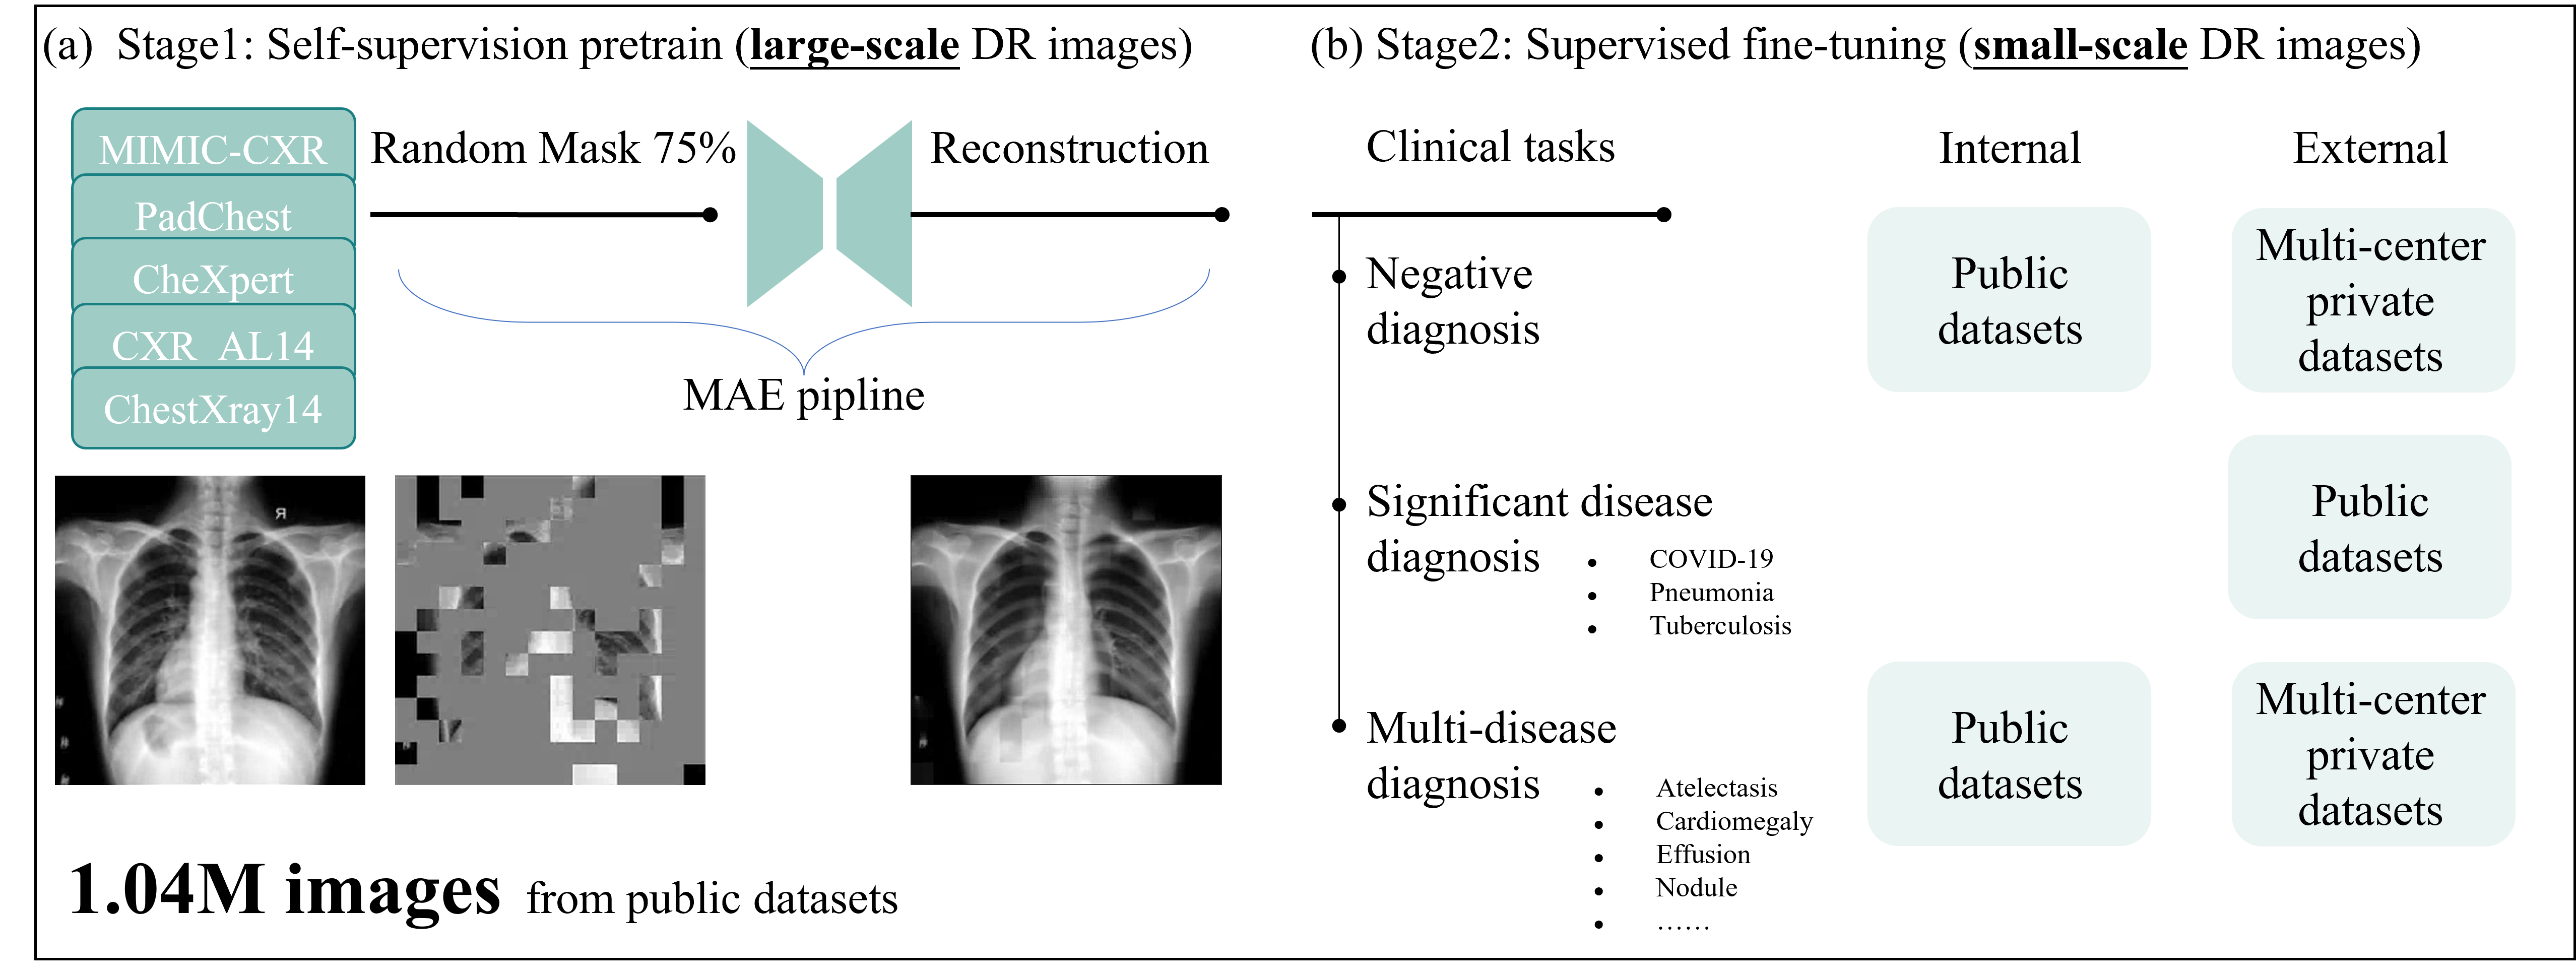

In this study, we introduced a novel SSL-based foundation model for chest X-ray (CXR) images, called CXRBase, and systematically evaluated its performance and generalizability across disease screening and diagnosis tasks. We constructed CXRBase from large-scale unlabelled CXR images using SSL methods (i.e., masked autoencoder), applied consecutively on both natural images (ImageNet-1k) and CXR images from public datasets, including a total of 1.04 million CXR images. Additionally, we supplemented the training with our in-house dataset. We adapted CXRBase to a series of challenging screening and disease diagnosis tasks by fine-tuning CXRBase with specific task labels and then validate its performance. CXRBase achieves consistently superior performance and label efficiency in adapting to these tasks, compared to competing specialist models, including that pre-trained on ImageNet-21k with traditional transfer learning. We further explored the interpretability of CXRBase’s disease localization performance through qualitative results and controlled experiments, highlighting how salient image regions align with established knowledge from the chest AI literature.

Refer to caption

Figure 1: Schematic of our proposed foundation model for Chest X-ray .

Figure 1 provides an overview of the construction and application of CXRBase. We developed a foundation model by self-supervision pretraining on a large-scale DR images. To build CXRBase, we assembled a dataset of 1.04 million CXR images, with 30.5% of images sourced from private datasets and 69.5% from public datasets (see Figure 2). After pretraining CXRBase using self-supervised on these CXR images, we extensively evaluated its performance and generalizability in adapting to various chest disease tasks. For the tasks of chest disease screening and diagnosis, we selected multi-center private datasets and publicly available datasets.